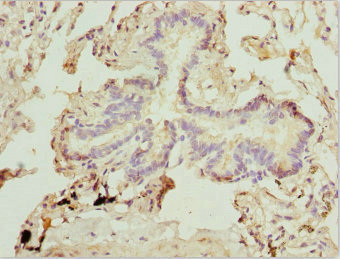

Immunohistochemistry of paraffin-embedded human lung tissue using CSB-PA064019ESR2HU at dilution of 1:100